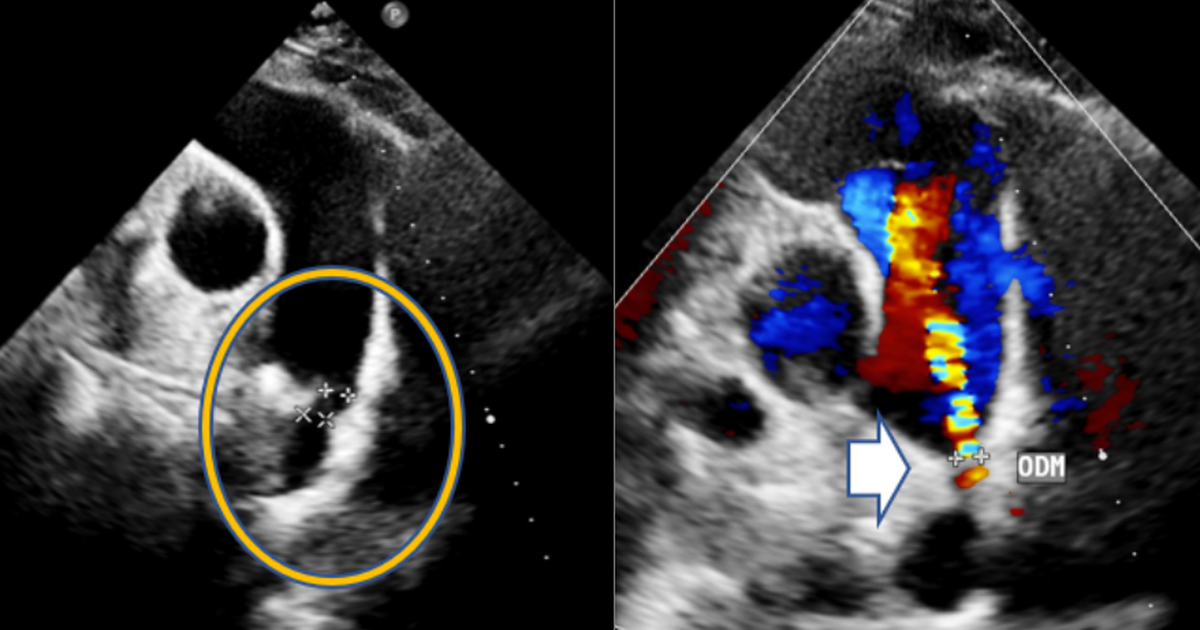

Ngay sau đó, chị N. được làm siêu âm tim. Kết quả cho thấy chị mắc còn ống động mạch - một dị tật tim bẩm sinh hiếm gặp ở người trưởng thành. Đây là tình trạng ống động mạch, vốn là mạch máu nối giữa động mạch chủ và động mạch phổi khi còn trong bào thai, không đóng lại sau khi trẻ chào đời. Ở trẻ sơ sinh, dị tật này thường được phát hiện và xử trí sớm, nhưng nếu tồn tại đến tuổi trưởng thành thì rất hiếm gặp, dễ gây ra nhiều biến chứng nguy hiểm như tăng áp phổi, suy tim...

Chưa đầy một giờ đồng hồ, ê kíp đã thành công bít hoàn toàn ống động mạch cho bệnh nhân. Hình ảnh siêu âm sau can thiệp cho thấy không còn dòng chảy bất thường, dụng cụ cố định vững chắc. Chị N. nhanh chóng cải thiện triệu chứng, ổn định và xuất viện chỉ sau 2 ngày.

Siêu âm tim đã giúp bác sĩ phát hiện dị tật tim bẩm sinh hiếm gặp, dù chị N. chỉ có triệu chứng mơ hồ và các chỉ số ban đầu hoàn toàn bình thường. Nhờ chẩn đoán chính xác, chị N. đã được can thiệp kịp thời và tránh được nguy cơ biến chứng nguy hiểm.

"Siêu âm tim là phương pháp không xâm lấn hàng đầu trong chẩn đoán dị tật tim bẩm sinh, cho phép nhận diện các bất thường cấu trúc tim từ đơn giản đến phức tạp. Vì vậy, đây được coi là công cụ sàng lọc và chẩn đoán quan trọng nhằm phát hiện sớm các dị tật tim bất thường", bác sĩ Hiệp chia sẻ thêm.

Tại Khoa Tim mạch - Tim mạch can thiệp BVĐK Hồng Ngọc sử dụng máy siêu âm Doppler tim hiện đại bậc nhất từ hãng Philips (Hà Lan) cho hình ảnh rõ nét, chi tiết. Qua đó, bác sĩ có thể đánh giá chính xác cấu trúc và chức năng tim, phát hiện sớm các bất thường và xây dựng phác đồ điều trị tối ưu, cá nhân hóa cho từng bệnh nhân.